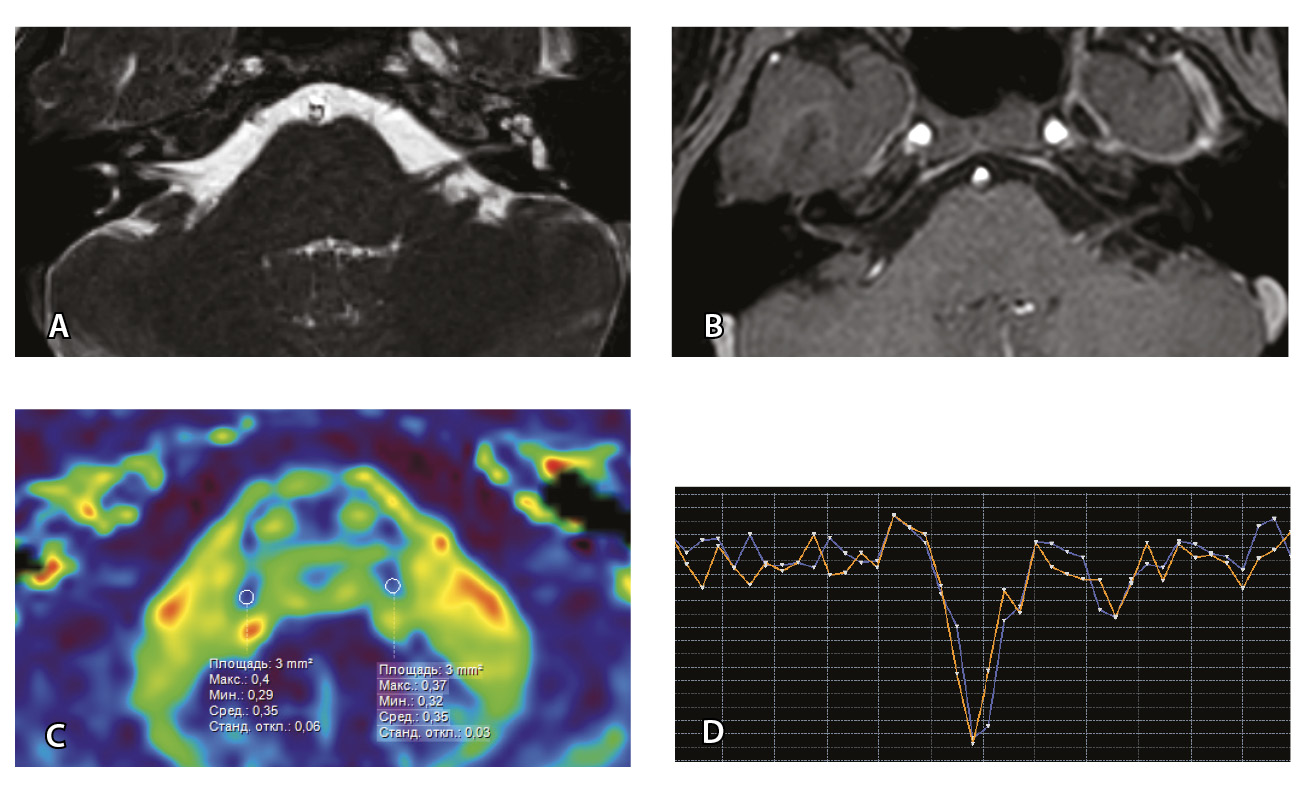

Рис. 7. Клиническое наблюдение 2, пациент 6 лет (А, Б, В, Г). Магнитно-резонансная томография (МРТ) головного мозга: А – прицельная T2-SSFP на область мосто-мозжечкового угла; Б – Т1-взвешенное изображение с контрастным усилением; В – диффузионно-тензорная МРТ (фракционная анизотропия, ФА); Г – Т2*-перфузия. На изображении T2-SSFP отмечается утолщение корешков лицевого, вестибуло-кохлеарного нервов во внутренних слуховых проходах (А, желтые стрелки) и интенсивное накопление ими контрастного вещества (Б, красные стрелки). На уровне моторных ядер лицевых нервов в заднем отделе варолиевого моста значения ФА симметричны (В), признаков гипо-/гиперперфузии не выявлено (Г).

Клиническое наблюдение 3, пациент 13 лет (Д, Е, Ж, З). МРТ головного мозга: Д – прицельная T2-SSFP на область мосто-мозжечкового угла; Е – Т1-взвешенное изображение с контрастным усилением; Ж – диффузионно-тензорная МРТ (ФА); З – Т2*-перфузия. На изображении T2-SSFP патологические изменения на уровне прохождения лицевых нервов во внутренних слуховых проходах не определяются (Д). В медиальном отделе правого полушария мозжечка определяется объемное образование, компримирующее стенку IV желудочка и задний отдел варолиевого моста без признаков васкуляризации (Е). На уровне моторных ядер лицевого нерва в заднем отделе варолиевого моста на изображениях ФА на стороне поражения отмечается минимальное уменьшение показателя ФА до 0,27 (Ж, черная стрелка) и признаки гипоперфузии (З, оранжевый график) по сравнению с контралатеральной стороной (З, синий график)

При этом в клиническом наблюдении № 2 из анамнеза жизни известен ранее установленный диагноз лимфобластного лейкоза в стадии ремиссии. В клиническом наблюдении № 3 значимых анамнестических сведений и данных в пользу атипичного течения ПБ получено не было.

Таким образом, при помощи информации, полученной при проведении МП-МРТ, в обоих случаях был установлен симптоматический характер НЛН, обусловленный развитием неопластических процессов. Оба пациента были направлены в профильные хирургические стационары для проведения дальнейшего лечения.